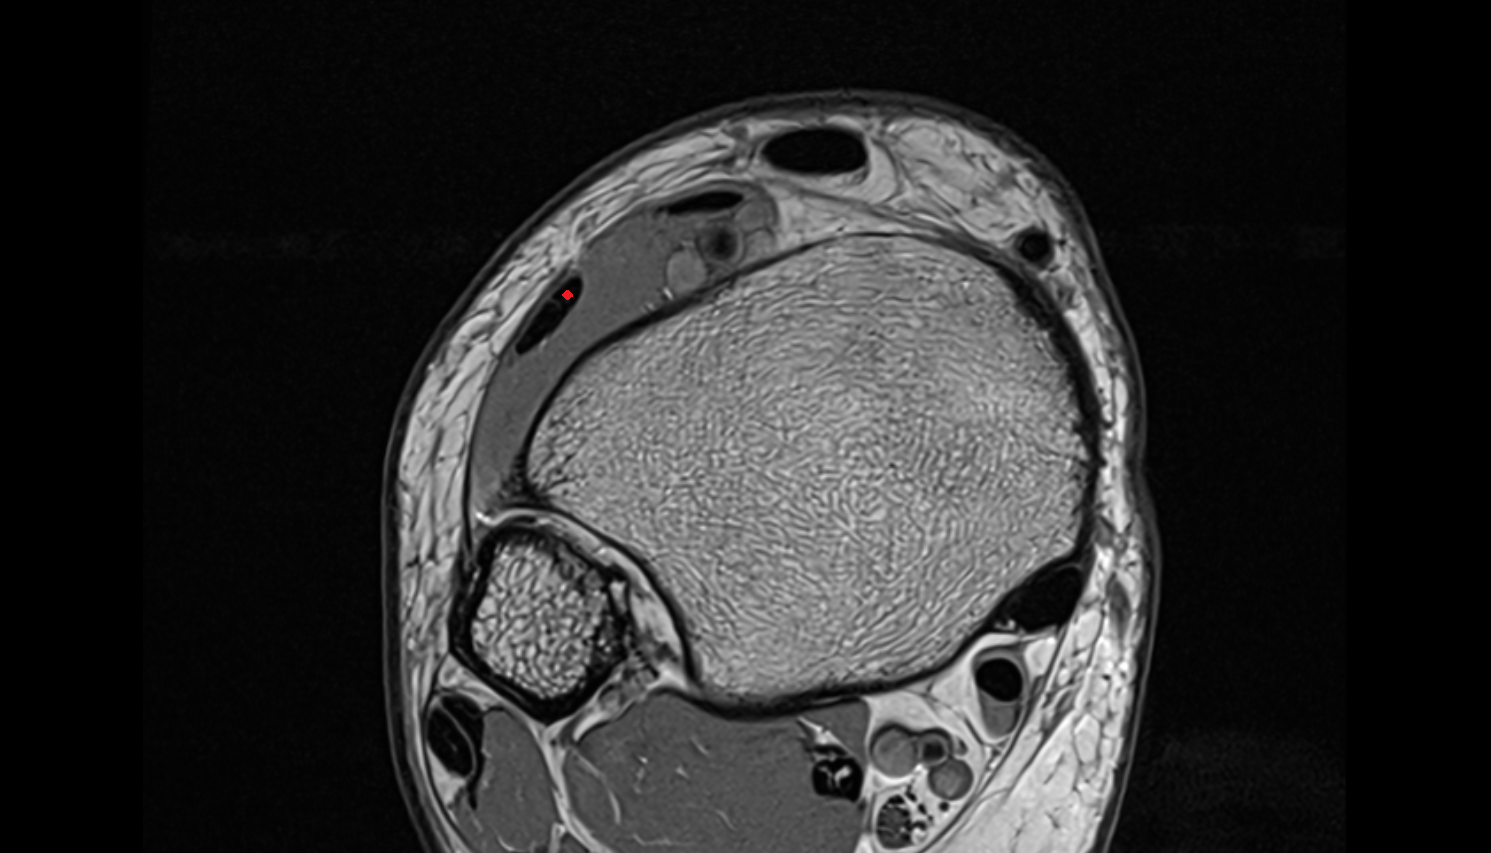

- Temporomandibular joint

- Mandibular condyle

- Mandibular fossa

- Articular disc of temporomandibular joint

- Articular eminence

- Intermediate zone of articular disc